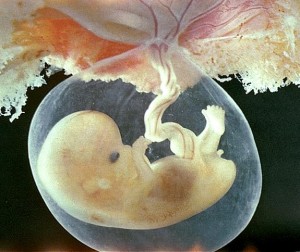

anne karnında bebek fotoları

4 haftalık bebek görüntüsü 25 haftalık bebek 25 görüntüsü

anne karnında 4 haftalık

anne karnında 4 haftalık